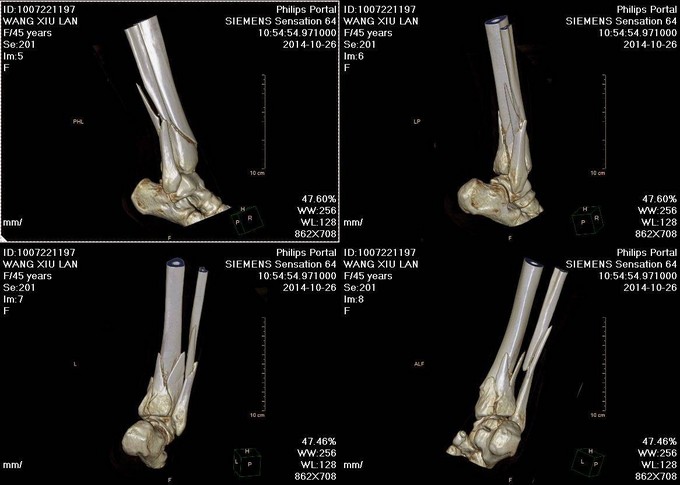

主诉:右小腿外伤后6天 现病史:患者2014-10-19日晚9时左右下楼时不慎摔倒,后于骨科医院就诊,行右下肢DR检查,提示右胫腓骨远端粉碎性骨折,后患者于骨科医院行夹板固定,并与当地祝家镇诊所输液治疗,具体治疗方案不详。后患者为求进一步诊治逐来我院。并以右胫腓骨远端粉碎性骨折收入院。患者病来一般状态可,二便正常,饮食睡眠可。

诊断:右胫腓骨远端粉碎性骨折 患者为右plion骨折,入院后局部肿胀明显,给予患肢抬高,冷敷,消肿等对症治疗,密切观察患肢皮肤情况,带皮肤条件良好的情况下,约2周后行右三踝骨折切开复位钢板内固定术。